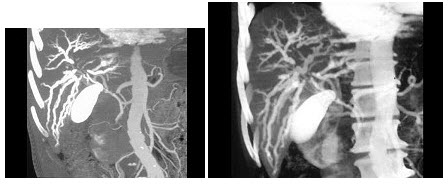

26、单项选择题

临床疑为胰头肿块,CT及CTA如图所示,最可能的诊断为()

A.胰腺癌

B.胰腺炎

C.假性动脉瘤

D.脓肿

E.以上都不是